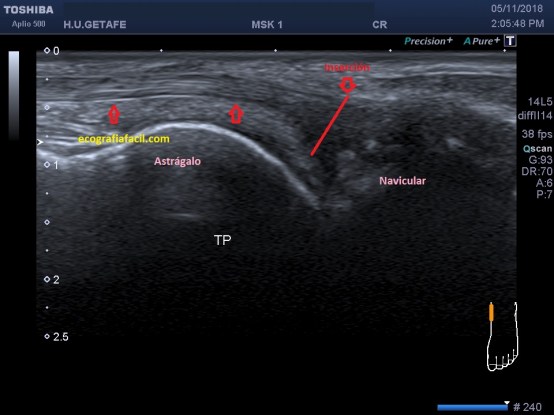

Inserta en el escafoides del pie, es una de sus inserciones, suele dar problemas aquí por patologías de tendinopatías de inserción.Se angula para insertar y se hace más grande, se ve hipoecogénico por la anisotropía, es normal.

Esta imagen es preciosa, está tomada en longitudinal como muy bien sabes, justo en la articulación de la tibia con el astrágalo, es fino y potente e inicia su descenso hacia la cara interna del pie para insertar.